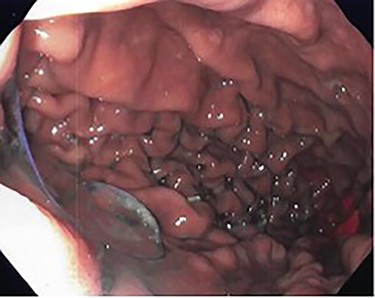

She underwent an upper gastrointestinal series that showed a normal-appearing stomach without any evidence of her prior gastroplasty, moderately sized hiatal hernia and slight delay in passage of contrast through the gastroesophageal junction (Fig. 1). On subsequent endoscopy, she was noted to have multiple loosely placed sutures within the gastric lumen along the greater curvature (Fig. 2), as well as a large-sized paraesophageal hernia.

Intraoperative endoscopy showing loose gastroplasty sutures along the greater curvature of the stomach.